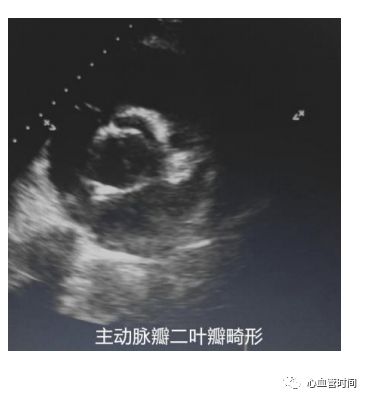

主动脉瓣观察有无钙化、畸形、狭窄、反流、脱垂。当存在二叶瓣畸形时,可见两个瓣叶

闭合点不居中、偏向一侧,瓣叶大小不同;狭窄时可见瓣叶

活动度减小,开放受限。且风湿性二尖瓣狭窄往往会累及主动脉瓣,则需注意观察是否合并主动脉瓣病变;脱垂时可见

一侧瓣叶于舒张期

脱向左室侧,往往存在大量反流。

主动脉瓣观察有无钙化、畸形、狭窄、反流、脱垂。当存在二叶瓣畸形时,可见两个瓣叶

闭合点不居中、偏向一侧,瓣叶大小不同;狭窄时可见瓣叶

活动度减小,开放受限。且风湿性二尖瓣狭窄往往会累及主动脉瓣,则需注意观察是否合并主动脉瓣病变;脱垂时可见

一侧瓣叶于舒张期

脱向左室侧,往往存在大量反流。

主动脉瓣可同时观察到主动脉瓣三个瓣叶。二叶瓣畸形时可见瓣口

闭合时呈线样,

开放时呈鱼口状,失去正常人字结构;主动脉瓣狭窄时可明显看出瓣叶开放受限,也可推测狭窄病因,如退行性、风湿性、二叶瓣畸形。

主动脉瓣可同时观察到主动脉瓣三个瓣叶。二叶瓣畸形时可见瓣口

闭合时呈线样,

开放时呈鱼口状,失去正常人字结构;主动脉瓣狭窄时可明显看出瓣叶开放受限,也可推测狭窄病因,如退行性、风湿性、二叶瓣畸形。